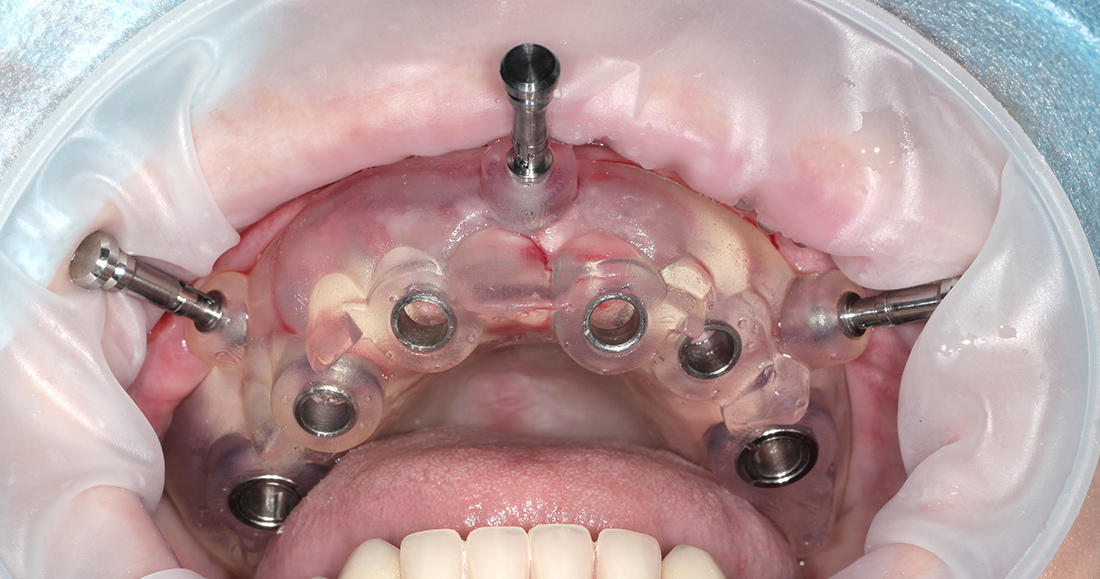

Дополнительным элементом планирования здесь было создание хирургического шаблона для установки имплантов, позволяющего перенести планирование лечения непосредственно в полость рта.

Предварительно вся операция по установке имплантов проводится виртуально в специальной программе: импланты располагаются в необходимых позициях, соответственно будущей ортопедической конструкции и доступной костной ткани. После этого виртуальный шаблон печатается на 3D-принтере и превращается уже в физический шаблон, через который и устанавливаются импланты.

В данной ситуации мы зафиксировали шаблон, установили 6 имплантов системы «ICX Templant» (Германия), провели наращивание костной ткани, установили окончательные головки «мультиюнит» и сняли слепки для изготовления временной конструкции. Через несколько дней был готов металлопластмассовый протез с винтовой фиксацией на шести имплантах.